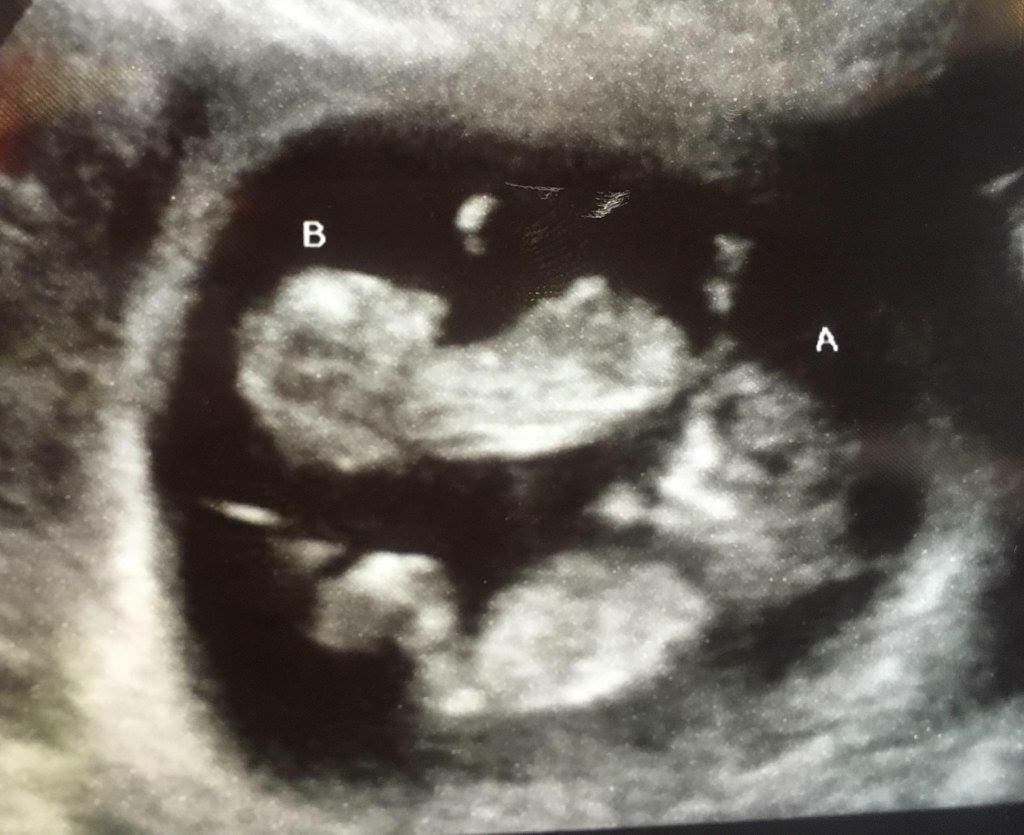

Ultrasound Photos of 10 Weeks Pregnant With Twins